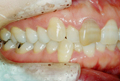

●主 訴 ― 叢生

●治療期間 ― 約3ヶ月

●治療内容 ― FLB舌側矯正装置、及びヘミオステオトミーによるスピード矯正(非抜歯ケース) |